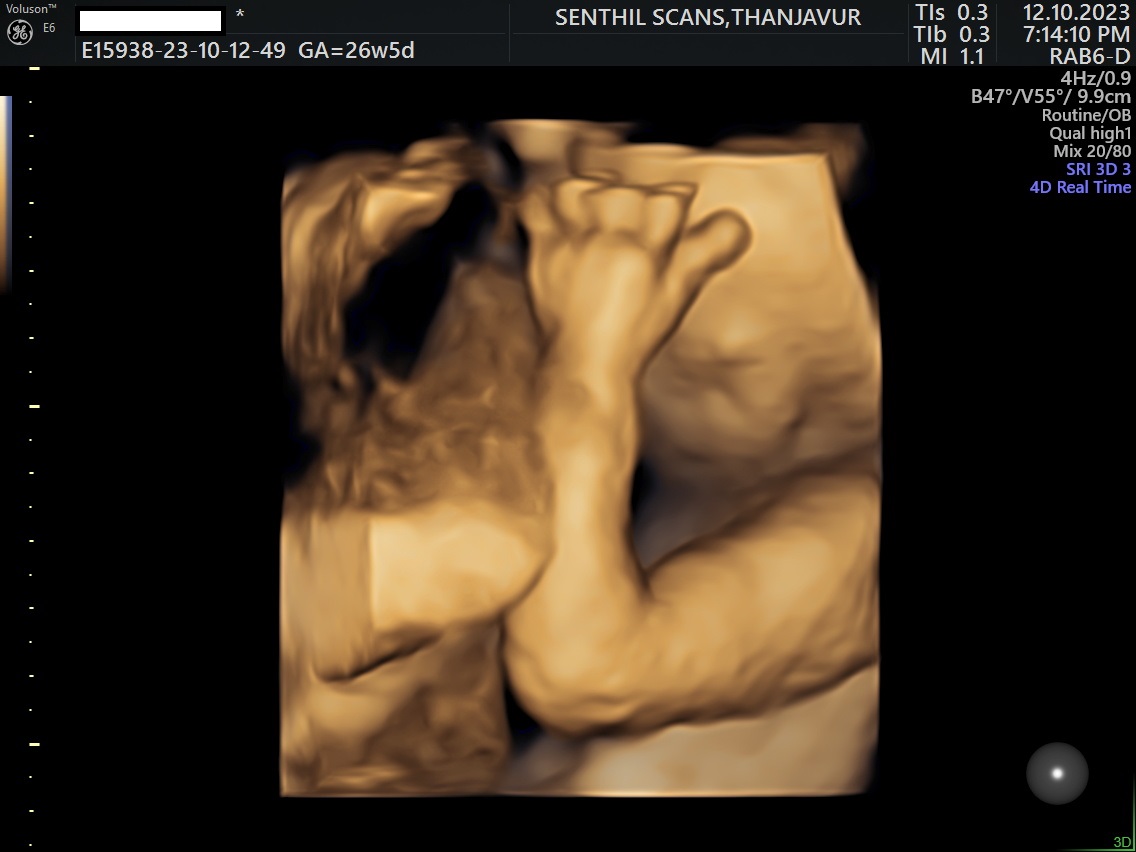

Ultrasound Scan